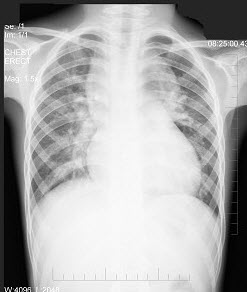

早产儿,男,生后4小时,生后出现呼吸困难,如图,最可能的诊断为()

A.新生儿肺炎

B.新生儿湿肺

C.新生儿肺出血

D.新生儿特发性呼吸窘迫综合症

E.胎粪吸入综合征

点击查看答案